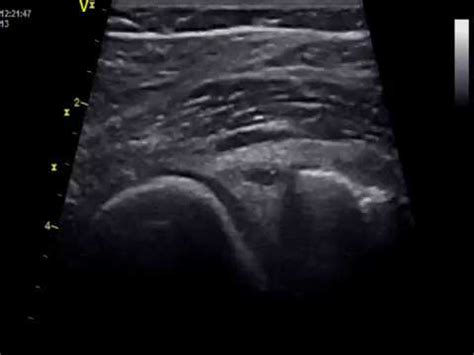

Повреждение мениска "ручка лейки" - YouTube

Разрыв мениска типа ручка лейки - YouTube

Хруст, щелчки и боль в колене. Почему? Разрыв м...